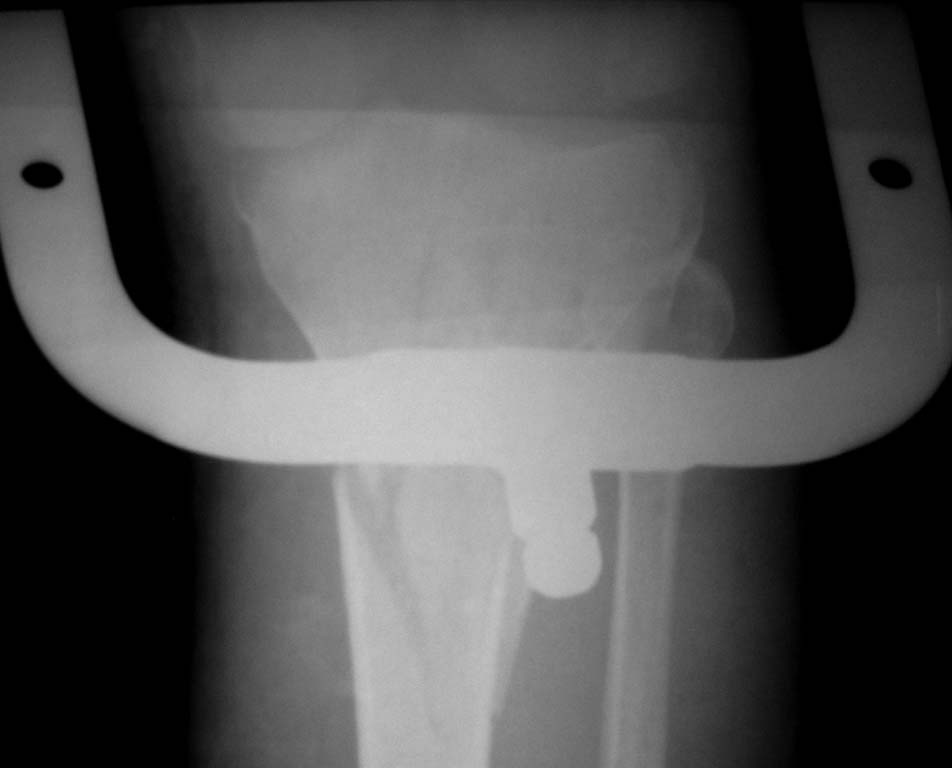

Нужен совет. Открытый перелом в\3 диафиза с оскольчатым переломом дистального метаэпифиза бедра. Закрытый оскольчатый внутрисуставной перелом проксимального отдела большеберцовой кости той же конечности.

При поступлении ПХО ран, скелетное вытяжение. Рана зажила первичным натяжением. Осложнилось правосторонней пневмонией. Предстоит выбрать тактику оперативного лечения и камими имплатнатами.